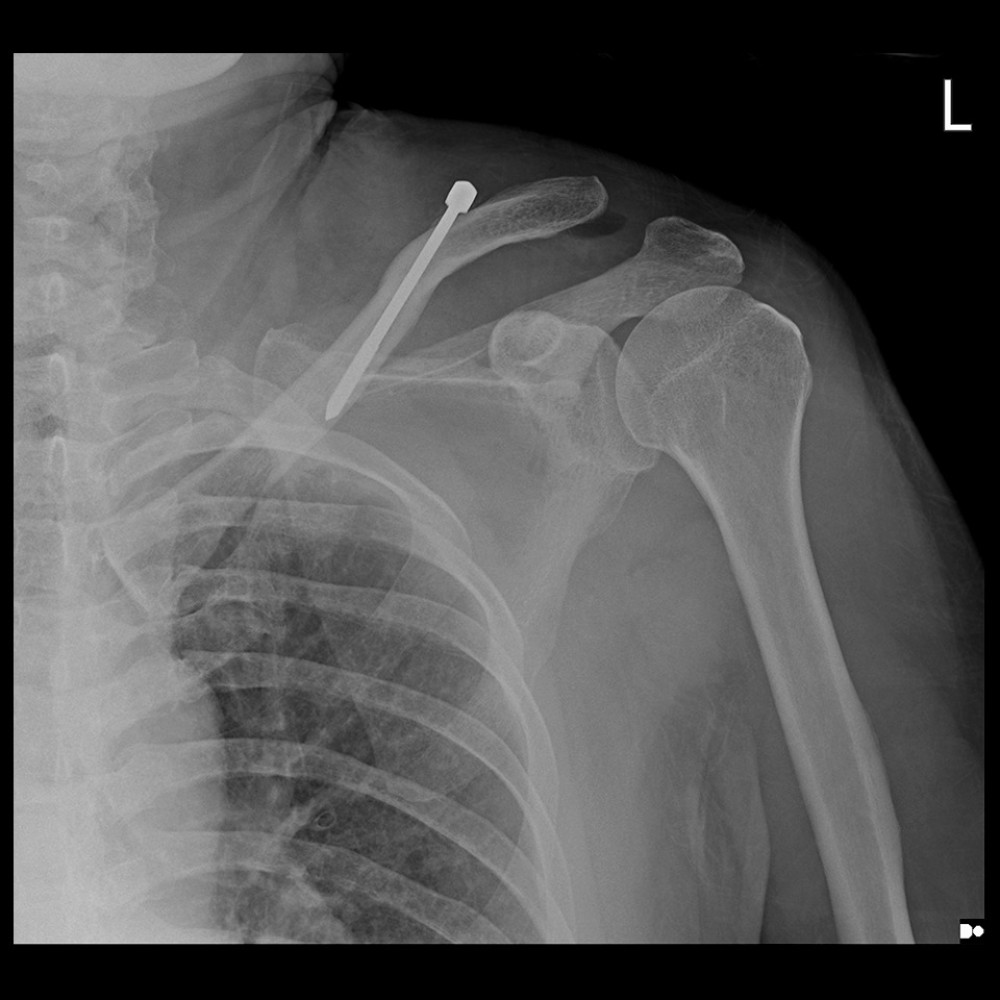

Clavicle Pin Fixation . Intramedullary devices, plates, and external. The purpose of this article is to demonstrate our technique of intramedullary (im) fixation of a midshaft clavicle fracture. An alternative to the current gold standard in operative treatment of displaced midshaft clavicle fractures (dmcf) using plate osteosynthesis, is internal fixation by means of intramedullary fixation devices. Operative fixation for acute displaced midshaft clavicle fractures provides improved functional outcomes and patient satisfaction over nonoperative treatment. Midshaft clavicle fractures are common traumatic injuries caused by a direct impact to the shoulder girdle and is most commonly seen in young, active adults.

Intramedullary devices, plates, and external. Midshaft clavicle fractures are common traumatic injuries caused by a direct impact to the shoulder girdle and is most commonly seen in young, active adults. An alternative to the current gold standard in operative treatment of displaced midshaft clavicle fractures (dmcf) using plate osteosynthesis, is internal fixation by means of intramedullary fixation devices. Operative fixation for acute displaced midshaft clavicle fractures provides improved functional outcomes and patient satisfaction over nonoperative treatment. The purpose of this article is to demonstrate our technique of intramedullary (im) fixation of a midshaft clavicle fracture.